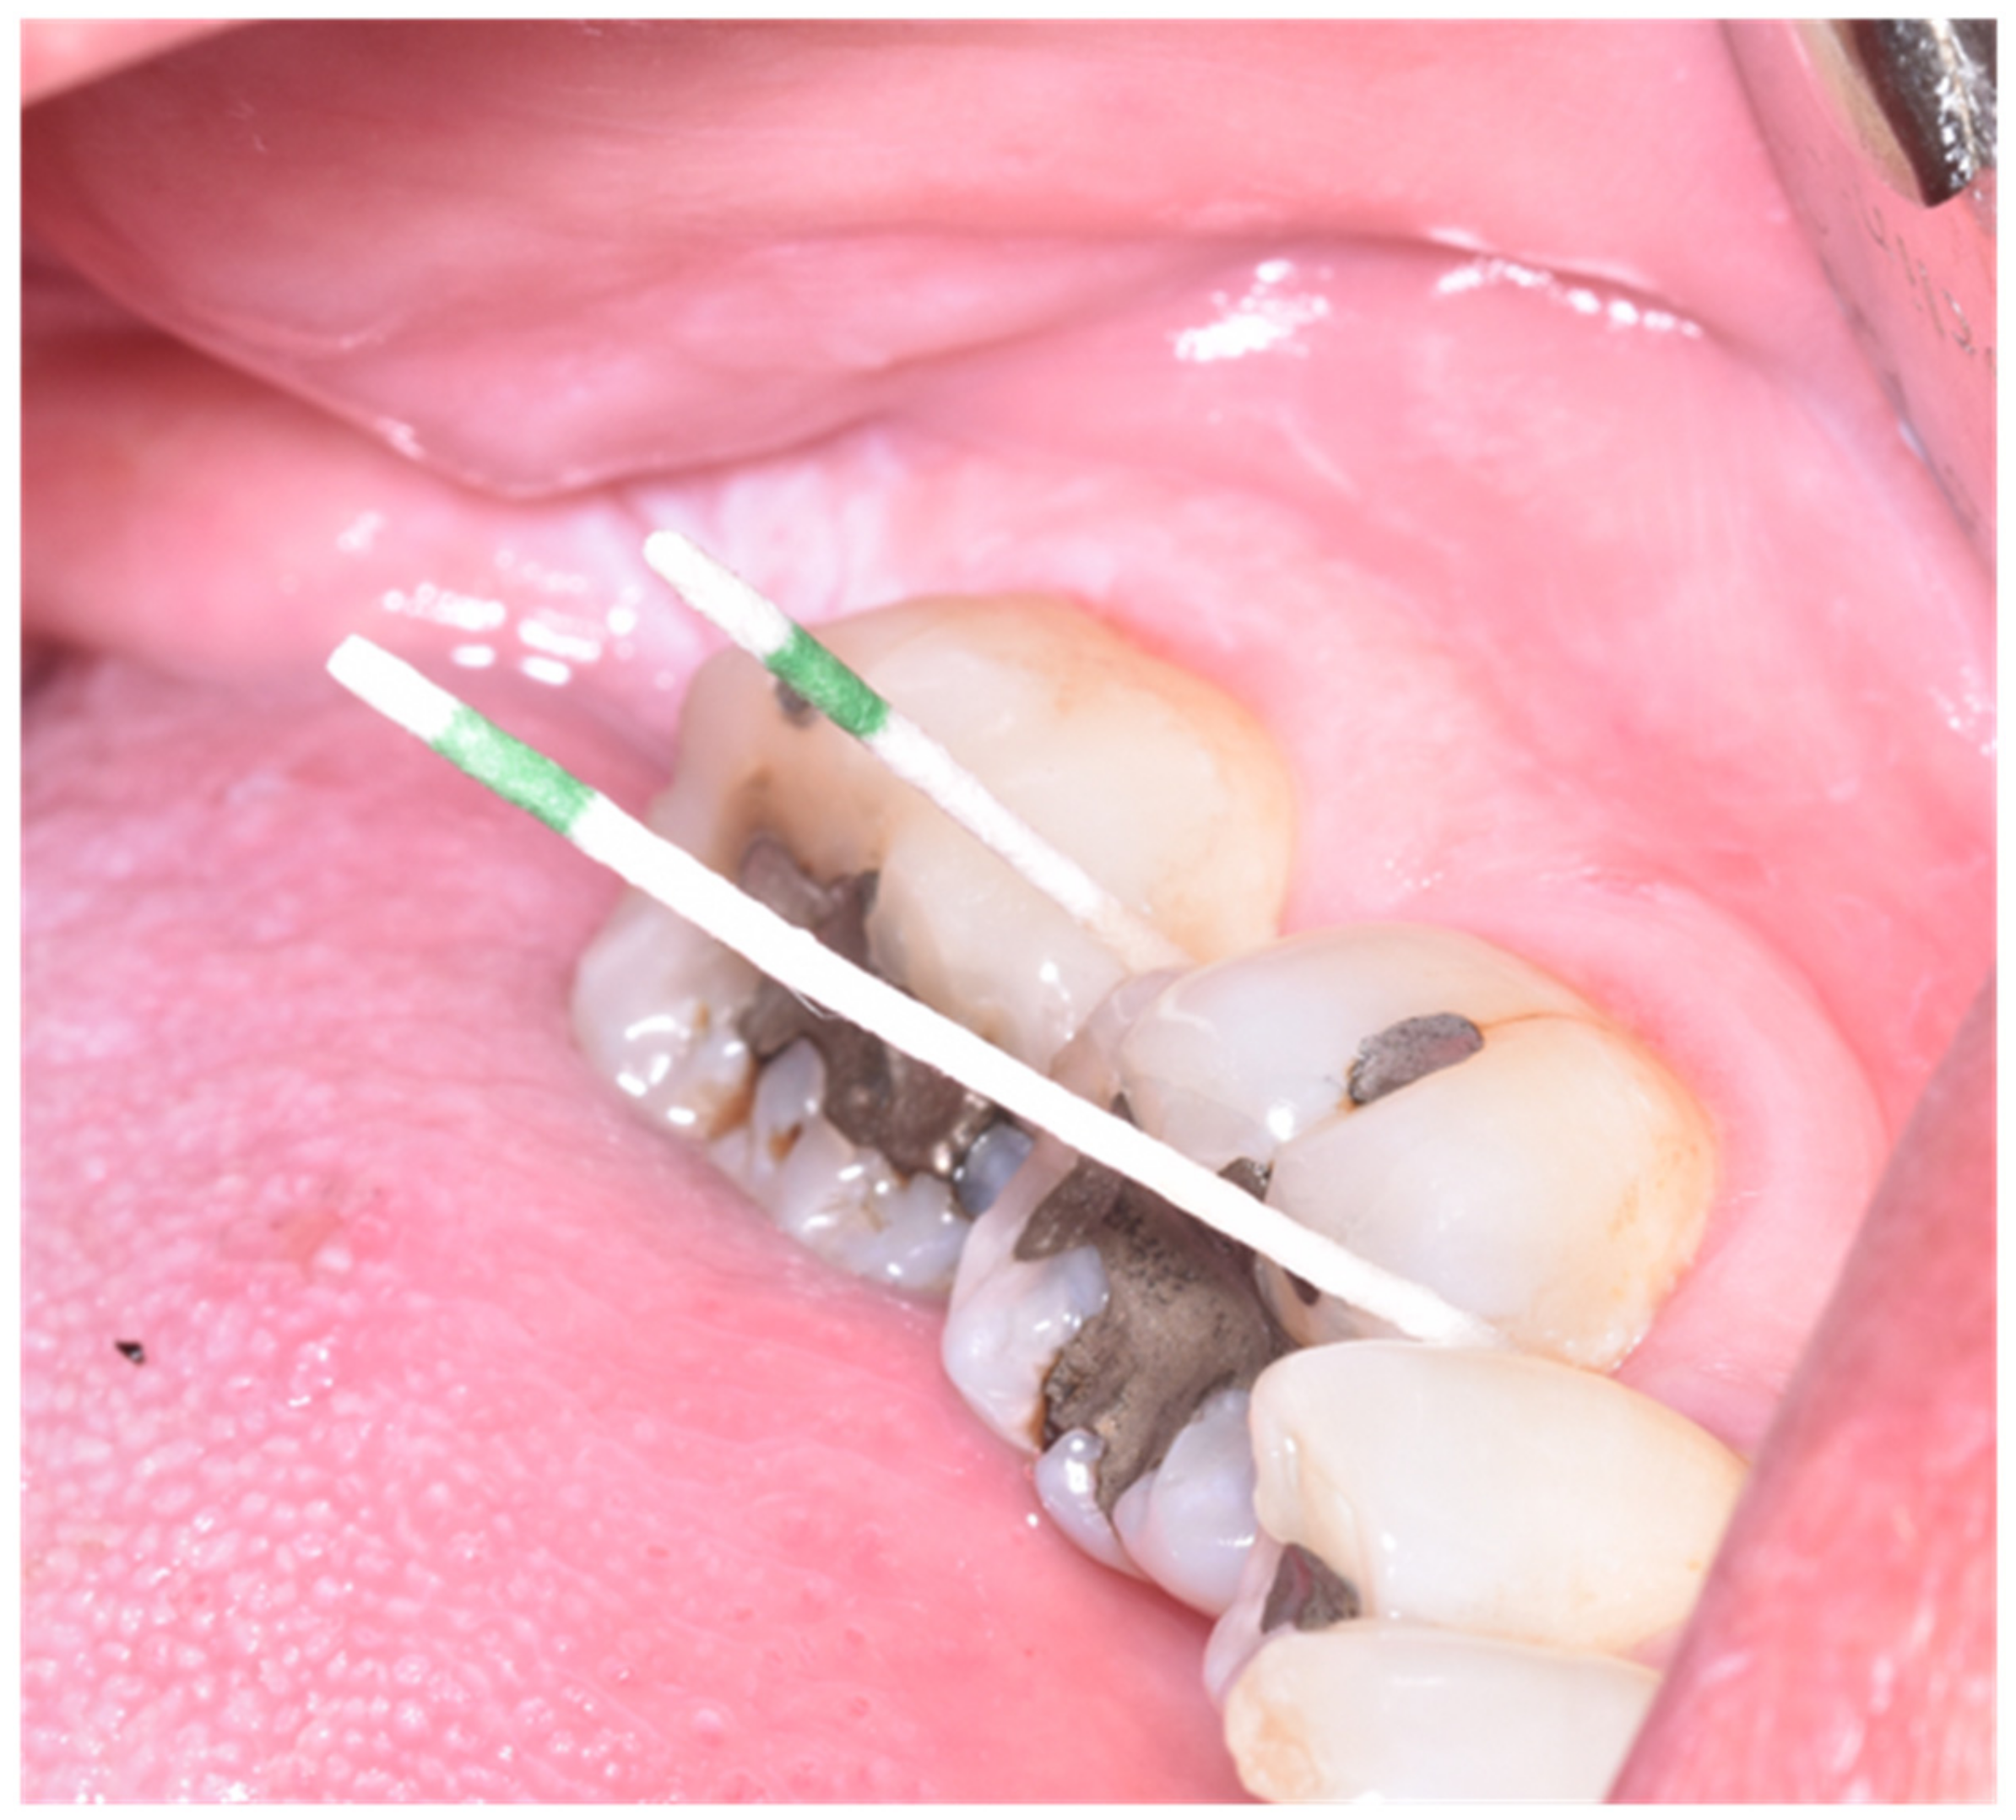

2.4. Intervention and Randomization